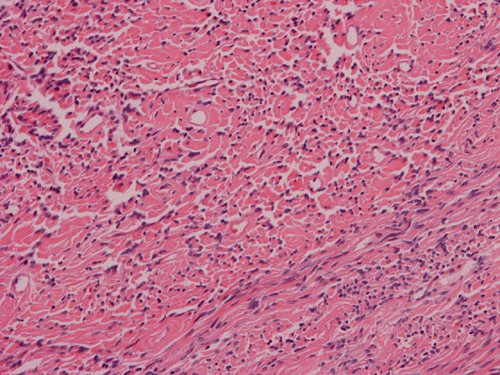

Histologically, the tumor is composed predominantly of strands of collagen fibers arranged in interlacing bundles (Panel F, G, H, I, J ). The histologic pattern is rather homogeneous among different areas and no area with particular hypocellularity or hypercellularity are found (Panel F). In between the collagen fibers are cigar shaped nuclei without high grade features (Panel J). The nuclei and the collagen fibers maintain an interesting regularly randomized relationship reminiscent of a checker board pattern (Panel I). A few small fragments of entrapped, mature bone are also found within the tumor. Mitoses and necrosis are not seen.

Immunohistochemistry demonstrated positive immunoreactivity in tumor cells for Vimentin, Bcl2 (Panel K) and CD34 (Panel L) but not CD99. The tumor cells are negative for muscle specific actin, desmin, S100, cytokeratin AE1/AE3, and epithelial membrane antigen (EMA).